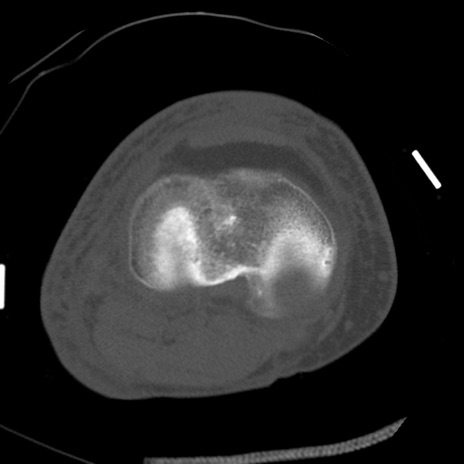

症例28 右膝関節CT(横断像)

右膝関節CT

冠状断像